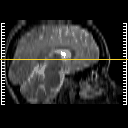

[Home][Help][Clinical] Slice 13

Click on sagittal image to select slice. Click on thin tickmark to change timepoint, or thick tickmark for overlay.